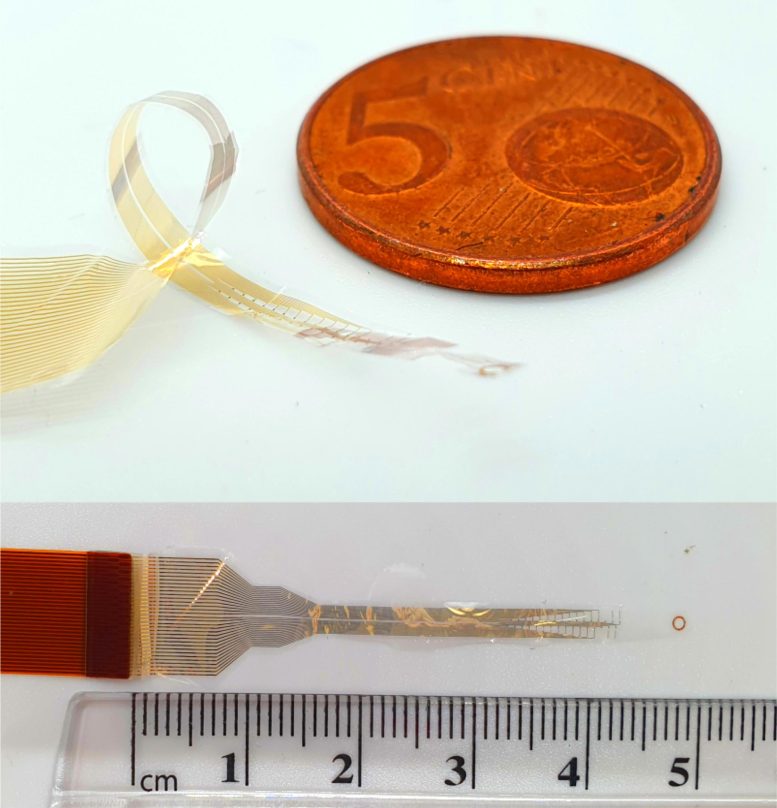

En s'inspirant de la microélectronique, les chercheurs ont développé un moyen d'obtenir des informations sur l'ensemble de la colonne vertébrale, en enroulant des implants très fins et à haute résolution autour de la circonférence de la moelle épinière. C’est la première fois qu’un enregistrement sûr à 360 degrés de la moelle épinière est possible – des approches antérieures pour la surveillance à 360 degrés utilisaient des électrodes qui transpercent la colonne vertébrale, ce qui peut provoquer des lésions médullaires.

Les dispositifs biocompatibles développés à Cambridge – d’une épaisseur de seulement quelques millionièmes de mètre – sont fabriqués à l’aide de techniques avancées de photolithographie et de dépôt de couches minces, et nécessitent une énergie minimale pour fonctionner.

Les appareils interceptent les signaux circulant sur les axones, ou fibres nerveuses, de la moelle épinière, permettant ainsi leur enregistrement. La finesse des appareils permet d'enregistrer les signaux sans causer de dommages aux nerfs, puisqu'ils ne pénètrent pas dans la moelle épinière elle-même.